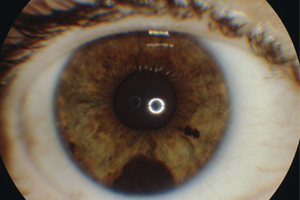

Fotodokumentation

Mit speziellen medizinischen Fotoapparaten werden sichtbare Veränderungen am vorderen oder hinteren Auge fotografisch festgehalten. Die Aufnahmen erfolgen digital, sind dadurch unbegrenzt speicherbar und jederzeit auffindbar. Jederzeit können davon auch Papierabzüge angefertigt werden. Die Fotografie ist die präziseste Vergleichsgrundlage für Langzeitbeobachtungen, da hier ein beobachterunabhängiger Vergleich über die Zeit erfolgen kann.

Vorderabschnittsfoto

Bestimmte Veränderungen, wie z. B. kleine Leberflecken, Blutgefäßgewächse oder Tumoren lassen sich nicht immer von vornherein klassifizieren, ob sie harmlos sind und deshalb belassen werden können, oder ob ihre Entfernung oder eine sonstige Therapiemaßnahme ratsam ist. In solchen Fällen entscheidet man sich häufig, den Befund in bestimmten Zeitabständen zu beobachten, um z. B. ein Wachstum oder eine Veränderung festzustellen, die dann ein aktives Eingreifen erfordern.

Wann empfiehl sich die Untersuchung?

Wenn es auf die Genauigkeit der Befunddokumentation und die beobachter- und zeitunabhängige objektive Vergleichsgrundlage ankommt.

Diese Untersuchung ist die exakteste Befundübermittelung an andere Ärzte, sei es zum Zweck der Einholung einer zusätzlichen Meinung oder beim Wechsel des behandelnden Arztes.

"Leberfleck" der Regenbogenhaut

Pterygium (Flügelfell der Bindehaut)